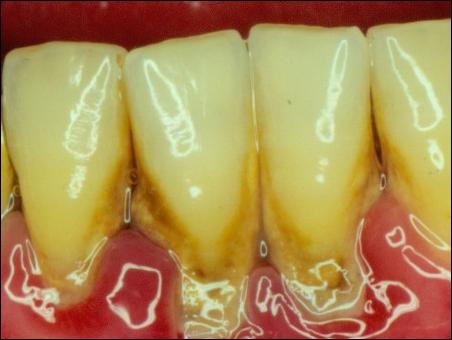

牙結(jié)石是如何附著在牙齦周圍的

掛滿了結(jié)石的牙齦組織紅腫